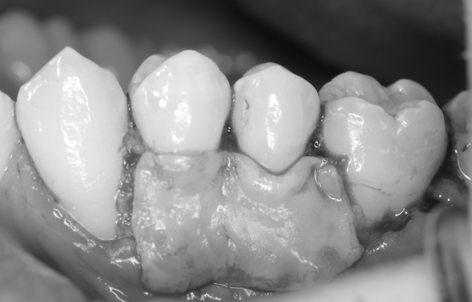

治療前

治療後